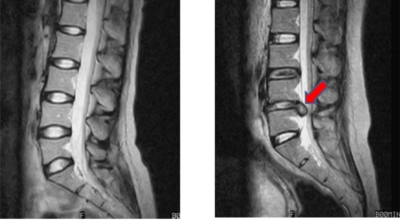

디스크는 일어선 상태에서는 중력을 받아 납작해져서 바깥쪽으로 약간 볼록한 형태가 된다고 합니다. 디스크는 그 특수한 구조 때문에 웬만한 힘이 가해져도 효율적으로 쿠션 역할을 할 수 있겠습니다. 그러나 급작스럽게 무거운 물건을 들어 올리거나, 부자연스러운 자세를 오랜 시간 취하면 디스크에 무리한 힘이 가해지면서 디스크가 밖으로 돌출이 되게 돼요. 심한 경우 디스크를 감싼 막이 터지면서 그 안에 있는 수핵이 튀어나오게 돼요.

디스크는 대개 후방이나 후외방으로 돌출되는데 이때 바로 곁에 있는 신경을 누르게 된다고 합니다. 돌출된 디스크는 척추의 어느 부위에나 일어날 수 있어요. 목에 생기면 '목 디스크', 등에 생기면 '등 디스크', 허리에 생기면 '허리 디스크'라고 부른다고 합니다.

이와 같이 디스크가 돌출되어 신경을 눌러 요통 또는 다리가 아프고 저린 증상을 유발하는 병을 '추간판 탈출증' 및 '디스크 탈출증'이라고도 불러요. 발생 빈도별로 보면 허리 디스크가 가장 흔합니다. 그다음이 목 디스크이지요. 등 디스크는 드문 병이라고 합니다.

허리디스크는 디스크의 퇴행성 변화나 외상에 의해 발병할 수 있지만 현대인의 경우 인체적 과부하로 인해 발병하는 경우도 있 다고 알려져 있는데, 대개 잘못된 자세나 운동부족, 잘못된 운동 자세가 원인이지요. 허리디스크는 보통 20~40대에 많이 발생하는데, 유전적 요인이나 큰 신장, 비만 흡연 사례 등이 허리디스크 발생 위험을 높이 다고 알려져 있어요.